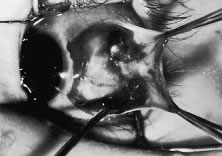

Recognized and unrecognized scleral perforation will occur. Reattachment of the muscle to the globe requires passing a needle within the sclera. The scleral coat of the globe is thinnest just posterior to the insertion of the rectus muscles. If the sclera becomes dry, it will thin further, and the blue color of the underlying uveal tissue will be visible. Needles with specially designed spatula tips are used to draw the sutures through the scleral tissue. Adequate illumination and magnification will facilitate this procedure. If the operation is prolonged, periodic wetting of the cornea and sclera with saline or a balanced salt solution will reduce thinning resulting from desiccation. In addition, adequate exposure and stabilization of the globe will reduce this complication. Scleral perforation also can occur when the needle is in the sclera and the surgeon attempts to lift the tip of the needle by placing torque on the needle with the needle holder (see Fig. 36). The fine-wire needles will bend, and, when the needle is released, the tip is directed posterior or into the sclera. Unexpected movement of the patient also may cause perforation of the globe (Fig. 78).

Fig. 78. This patient unexpectedly moved when the muscle was being cut from its insertion. The sclera had a small tear that was closed with two 8-0 silk sutures.